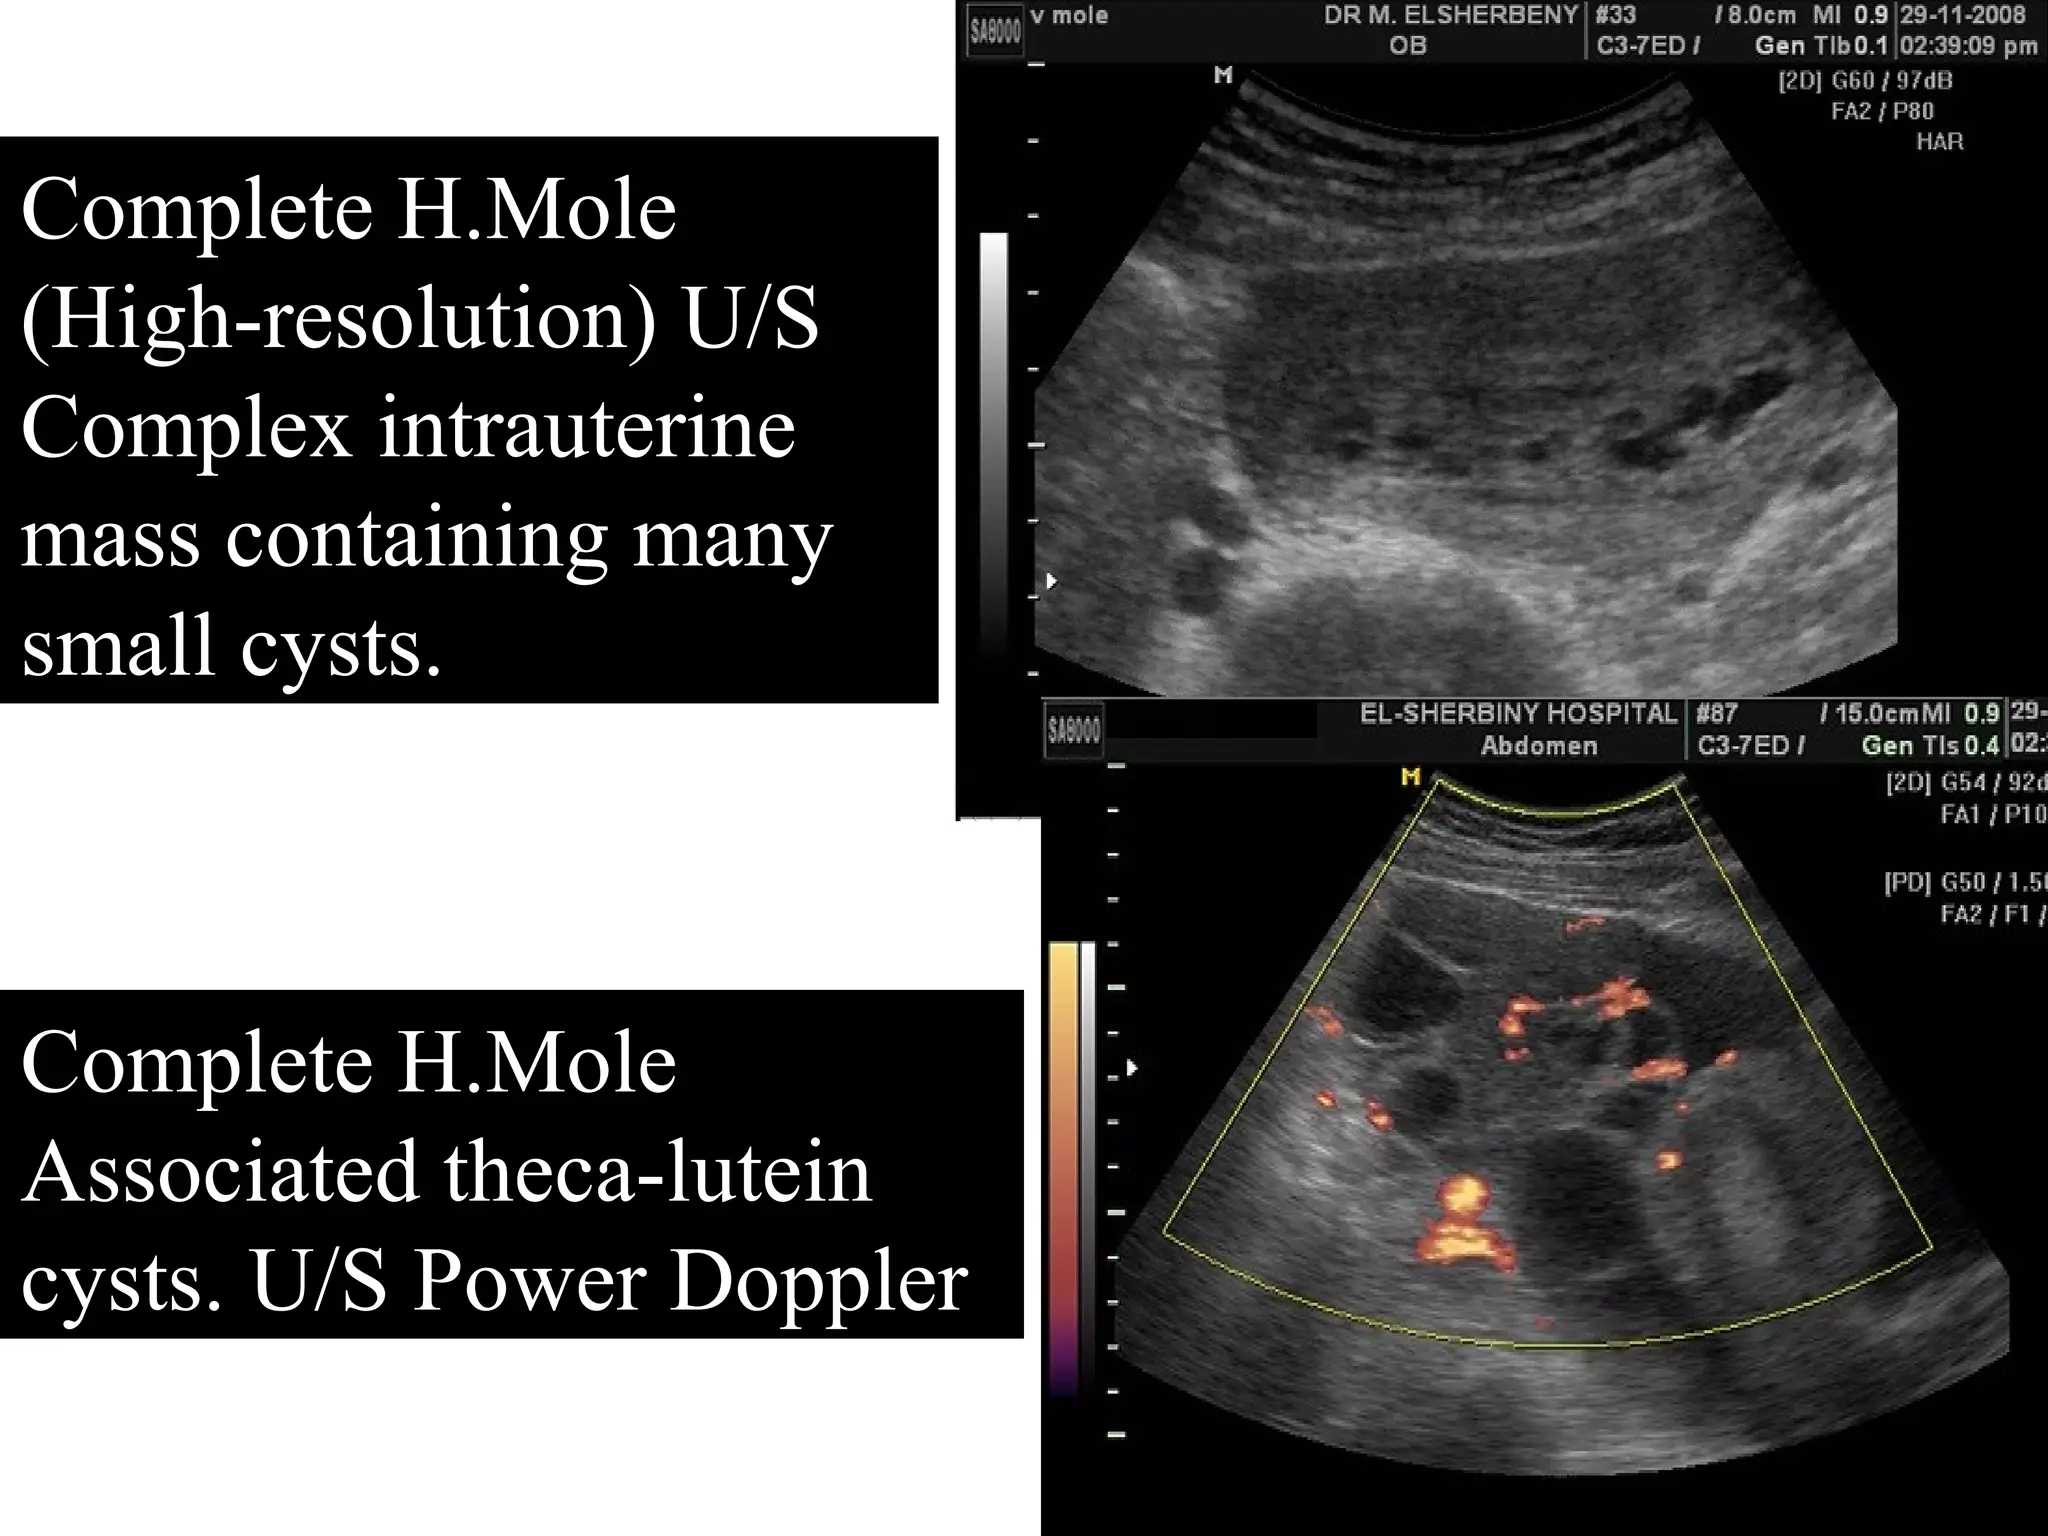

Case Review: Ultrasound Of Complete Molar Pregnancy | Radiology

Case Review: Ultrasound of Complete Molar Pregnancy | Radiology www.everand.com

pregnancy molar ultrasound mole complete trophoblastic disease uterus enlarged transabdominal gestational westjem pelvis echogenic endometrial arrow cystic areas multiple within

Molar pregnancy ultrasound evacuation disease gestational. Case review: ultrasound of complete molar pregnancy. Molar pregnancy